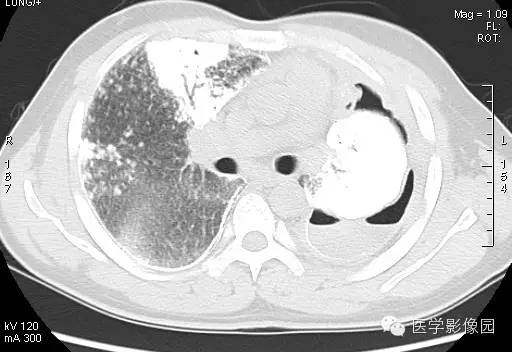

【病例】尘肺1例X线及CT影像表现

男性,36岁,镀锌工作史1年。

小结节影:多为双肺弥漫性或散在小结节影,表现为类圆形影,边界清晰,以中下肺为主,背侧多见。

大阴影:多为块状大阴影,表现为不规则卵圆形影,边缘凹凸不平,多有粗大索条影,伴疤痕性肺气肿,其内可见点状、斑片状钙化,坏死或空洞。

胸膜改变:可见胸膜肥厚、粘连及钙化缘怨例。